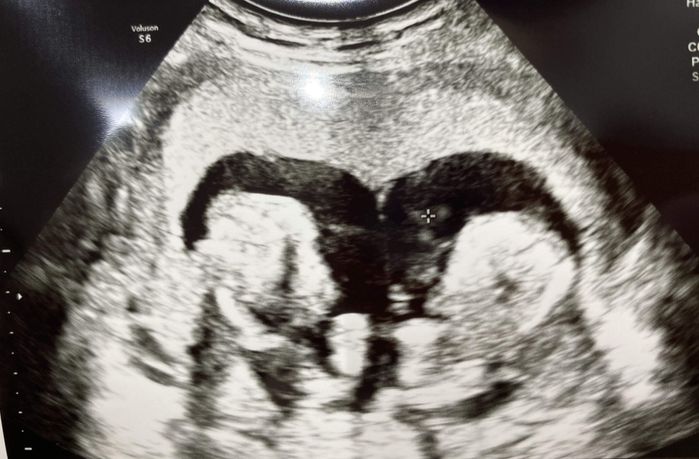

毎日、医師や看護師さんがおなかの赤ちゃんの心音を確認してくれました。その音を聞いて『今日も生きている』と少しだけほっとする日々。エコー検査の日には、動いている姿を見ることもできました。幸運にも大きな変化はなく、2人の心臓は動き続けてくれました」(河原さん)

「妊娠22週を過ぎた日の診察で、医師から『正直、よくも悪くもならずこの状況が続くと思いませんでした』と言われたんです。その言葉に、うれしくて笑ってしまいました。2人の生命力はすごいな! って。

『もうしばらくおなかにいてね』と心の中で2人に話しかけていましたが、23週に入った日、また大量の水が流れてきました。三男のほうも破水したのです。2人とも破水してしまったら、もうおなかの中に長くはいられません。